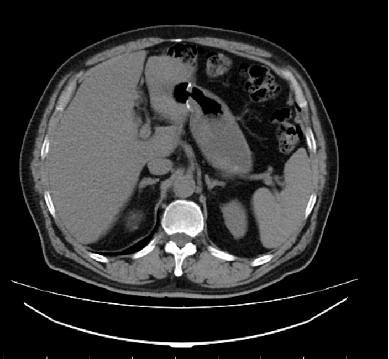

影像学检查:

胸腹盆CT:未见明显异常。 肠镜:直肠距肛门4cm见不规则肿块,约3*1.5cm,表面高低不平。

MR:1、直肠癌(T3可能),与右侧肛提肌关系密切,考虑1、炎性渗出粘连2、侵犯待排2、慢性膀胱炎3、前列腺增生。

2017-09 MR:

腹腔镜探查腹腔,见:肝脏表面,胰腺、腹腔、盆腔无肉眼可见转移结节,盆腔未见明显腹水。肿瘤位于直肠下段腹膜返折处,肿瘤侵及浆膜外,与周围组织粘连成团,冰冻骨盆。行乙状结肠造口术。

影像学复查:( XELIRI方案)

2018-01: 两肺气肿,左肾小结石,肝左叶考虑异常灌注,腹腔,盆腔未见复发转移病灶。

2018-03: 两肺气肿,两肺下叶纤维灶,肝左叶考虑异常灌注,慢性膀胱炎,前列腺钙化,盆腔未见复发转移病灶。

2018-06:肝脏局部灌注异常,实质内多发小斑片状影。

2018年06月:肝脏局部灌注异常,实质内多发小斑片状影

2018年09月平扫:未见特殊异常

胸腹盆增强CT(2020-05-08):直肠癌治疗术后,左下腹造瘘术后,肝脏多发转移较前增多增大,双肺气肿,主动脉及冠状动脉硬化,双肾囊肿